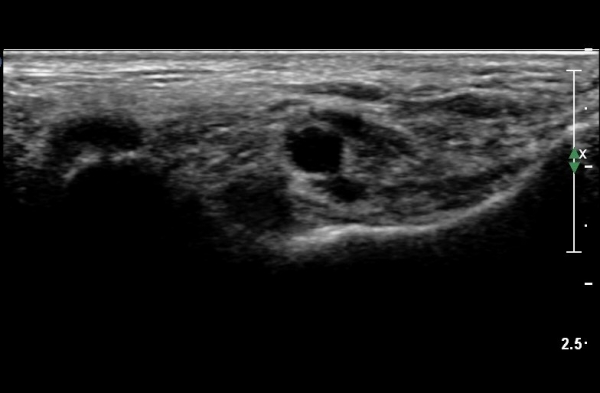

ŽÃËÀÚ¸¦ Á¶±Ý ¸»´ÜÀ¸·Î À̵¿ÇÏ´Ï Èİæ°ñ½Å°æÀÌ ³»ÃøÁ·Àú½Å°æ°ú ¿ÜÃøÁ·Àú½Å°æÀ¸·Î ºÐÁöÇÑ´Ù(»çÁø 2).